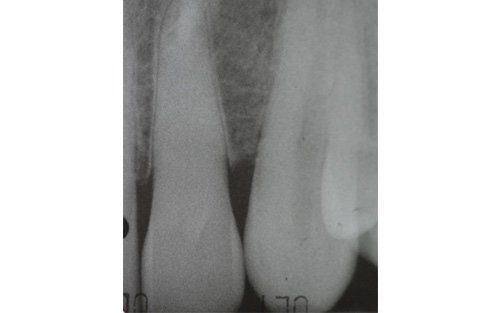

This treatment should be reserved for teeth that have irreversible pulp pathology (the nerve of the tooth) or an infection of the dental canals that has caused an abscess (acute apical periodontitis) or a granuloma (chronic apical periodontitis). While in the first two cases the tooth is very painful and the patient immediately seeks the dentist, the case of the chronic form is often silent, and therefore the patient may not notice anything for a medium to long period of time. In such conditions, it is only an X-ray image, taken during routine check-ups, that detects its presence. Root canal therapy can be completed by placing a latest-generation post inside the canal, as a means of retaining the material used for the reconstruction of the tooth. It will be up to the clinician to decide whether or not the restoration requires this additional anchoring system.